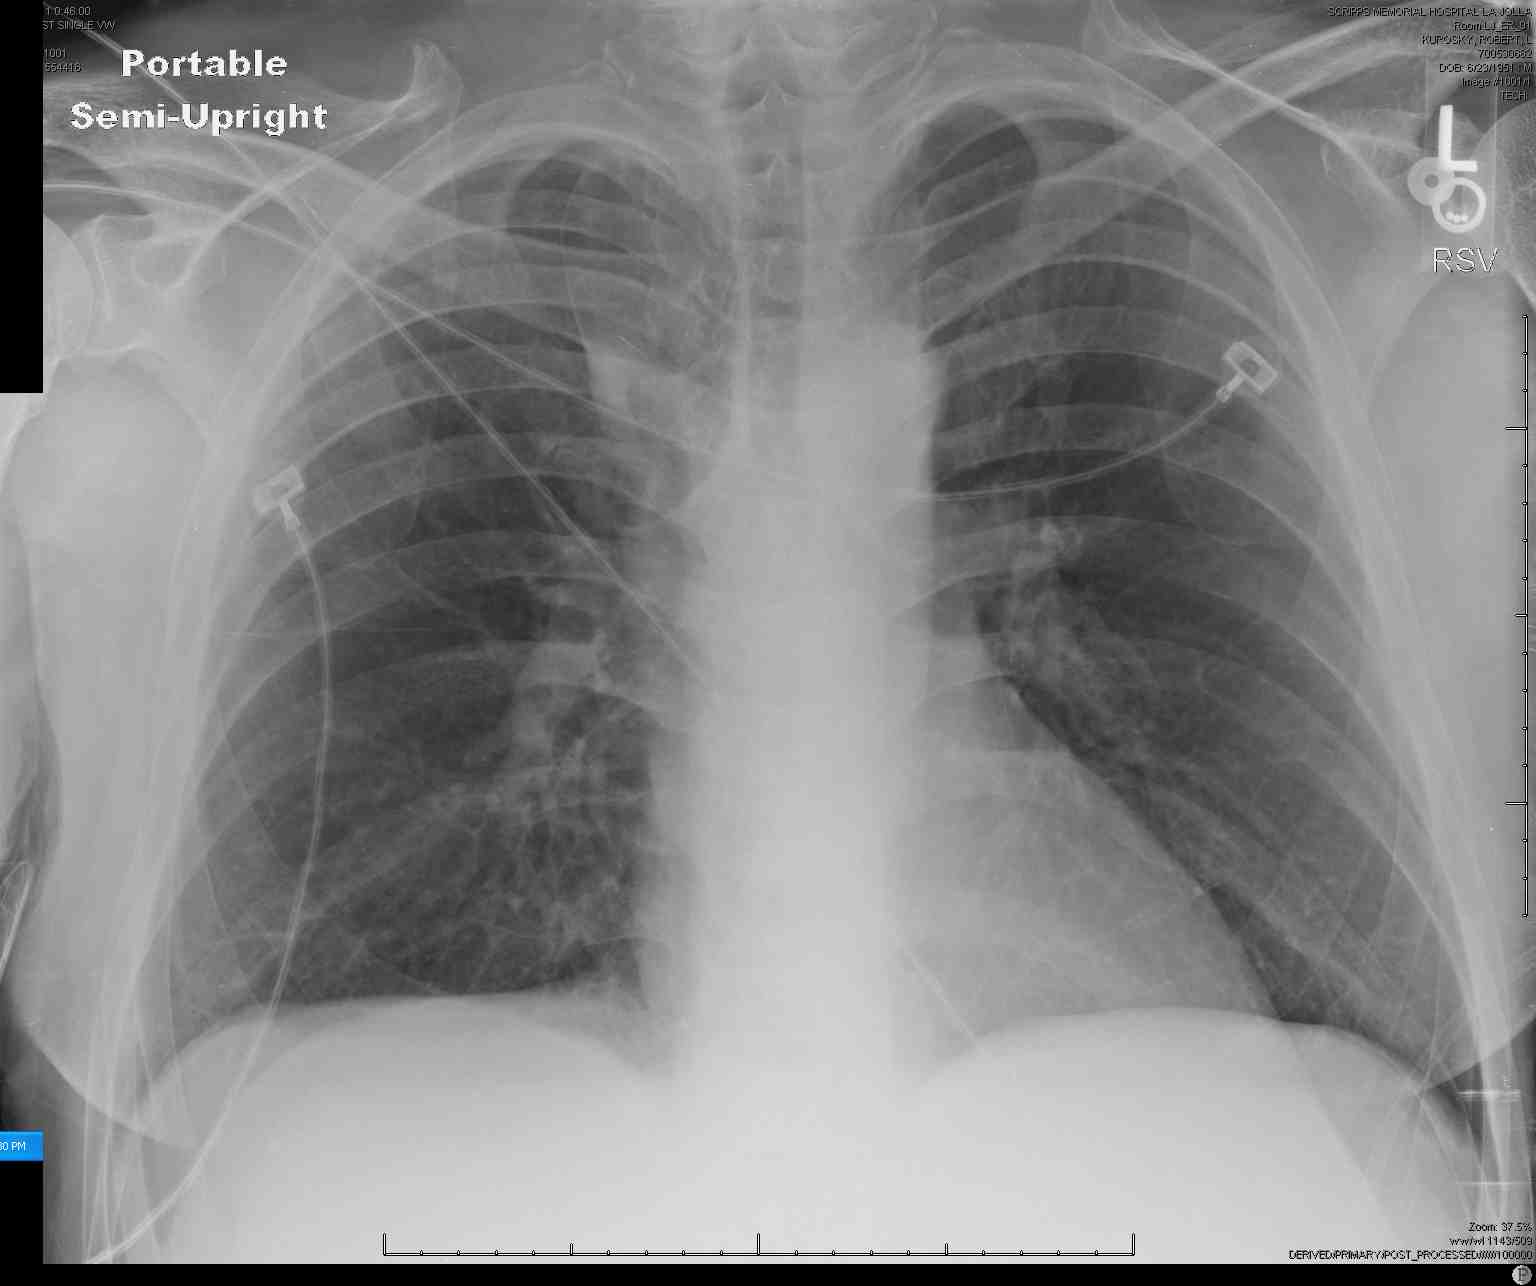

Azygos Lobe